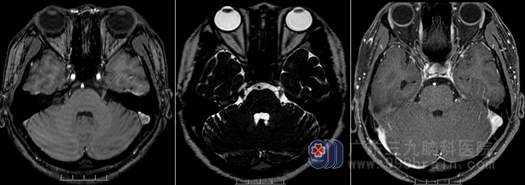

住院后,外十科团队在科主任欧阳辉教授带领下给王女士进行了更详细的检查,MR显示:左侧三叉神经颅内段上方有一条细小血管水平骑跨伴行,疑为三叉神经压迫的责任血管。结合王女士的病史,外十科团队对治疗方案进行了讨论,一致认为微创手术是最佳的治疗方案,三叉神经根显微血管减压术是最佳的手术方式。在得到王女士和其家人的同意之后,外十科的手术组的医护人员进行了周密的术前准备。